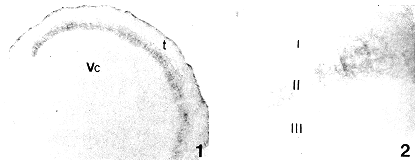

在三叉初级传入路径中,BSI-B4标记的神经元为蓝绿色,标记的三叉初级传入路径终末仅见于三叉神经脊束核的尾侧亚核(图1,2,Vc),在脊间亚核和吻侧亚核均无标记终末分布,Vc内的标记终末在Ⅰ、Ⅱ层内均有分布,以第Ⅱ层尤其是内侧部最为密集。标记终末光滑而不呈念珠状。在三叉神经节(图3),标记的神经节细胞多为圆形和卵圆形,细胞的突起细长,胞核多淡染,核膜和胞膜深染,在核周围分布有强阳性标记颗粒。BSI-B4标记细胞与Nissl染色细胞的剖面积比较见附表,对表中数据进行Bartlett和团体t检验,结果表明:BSI-B4标记细胞平均剖面积为20.55μm2,全部三叉神经节细胞的平均剖面积为45.34μm2,t=21.92,P<0.001,即BSI-B4标记的细胞为中小型细胞。在三叉神经中枢端,蓝绿色的标记纤维呈平行排列。在三叉神经脊束内标记纤维呈点状分布。

图1 BSI-B4标记的三叉初级传入纤维及终末在三叉神经尾侧亚核(VC)内的分布。t.三叉神经脊束 ×45

图2 为图1的局部放大,显示BSI-B4标记纤维及终末的形态.Ⅰ~Ⅲ.Vc的Ⅰ~Ⅲ层 ×150